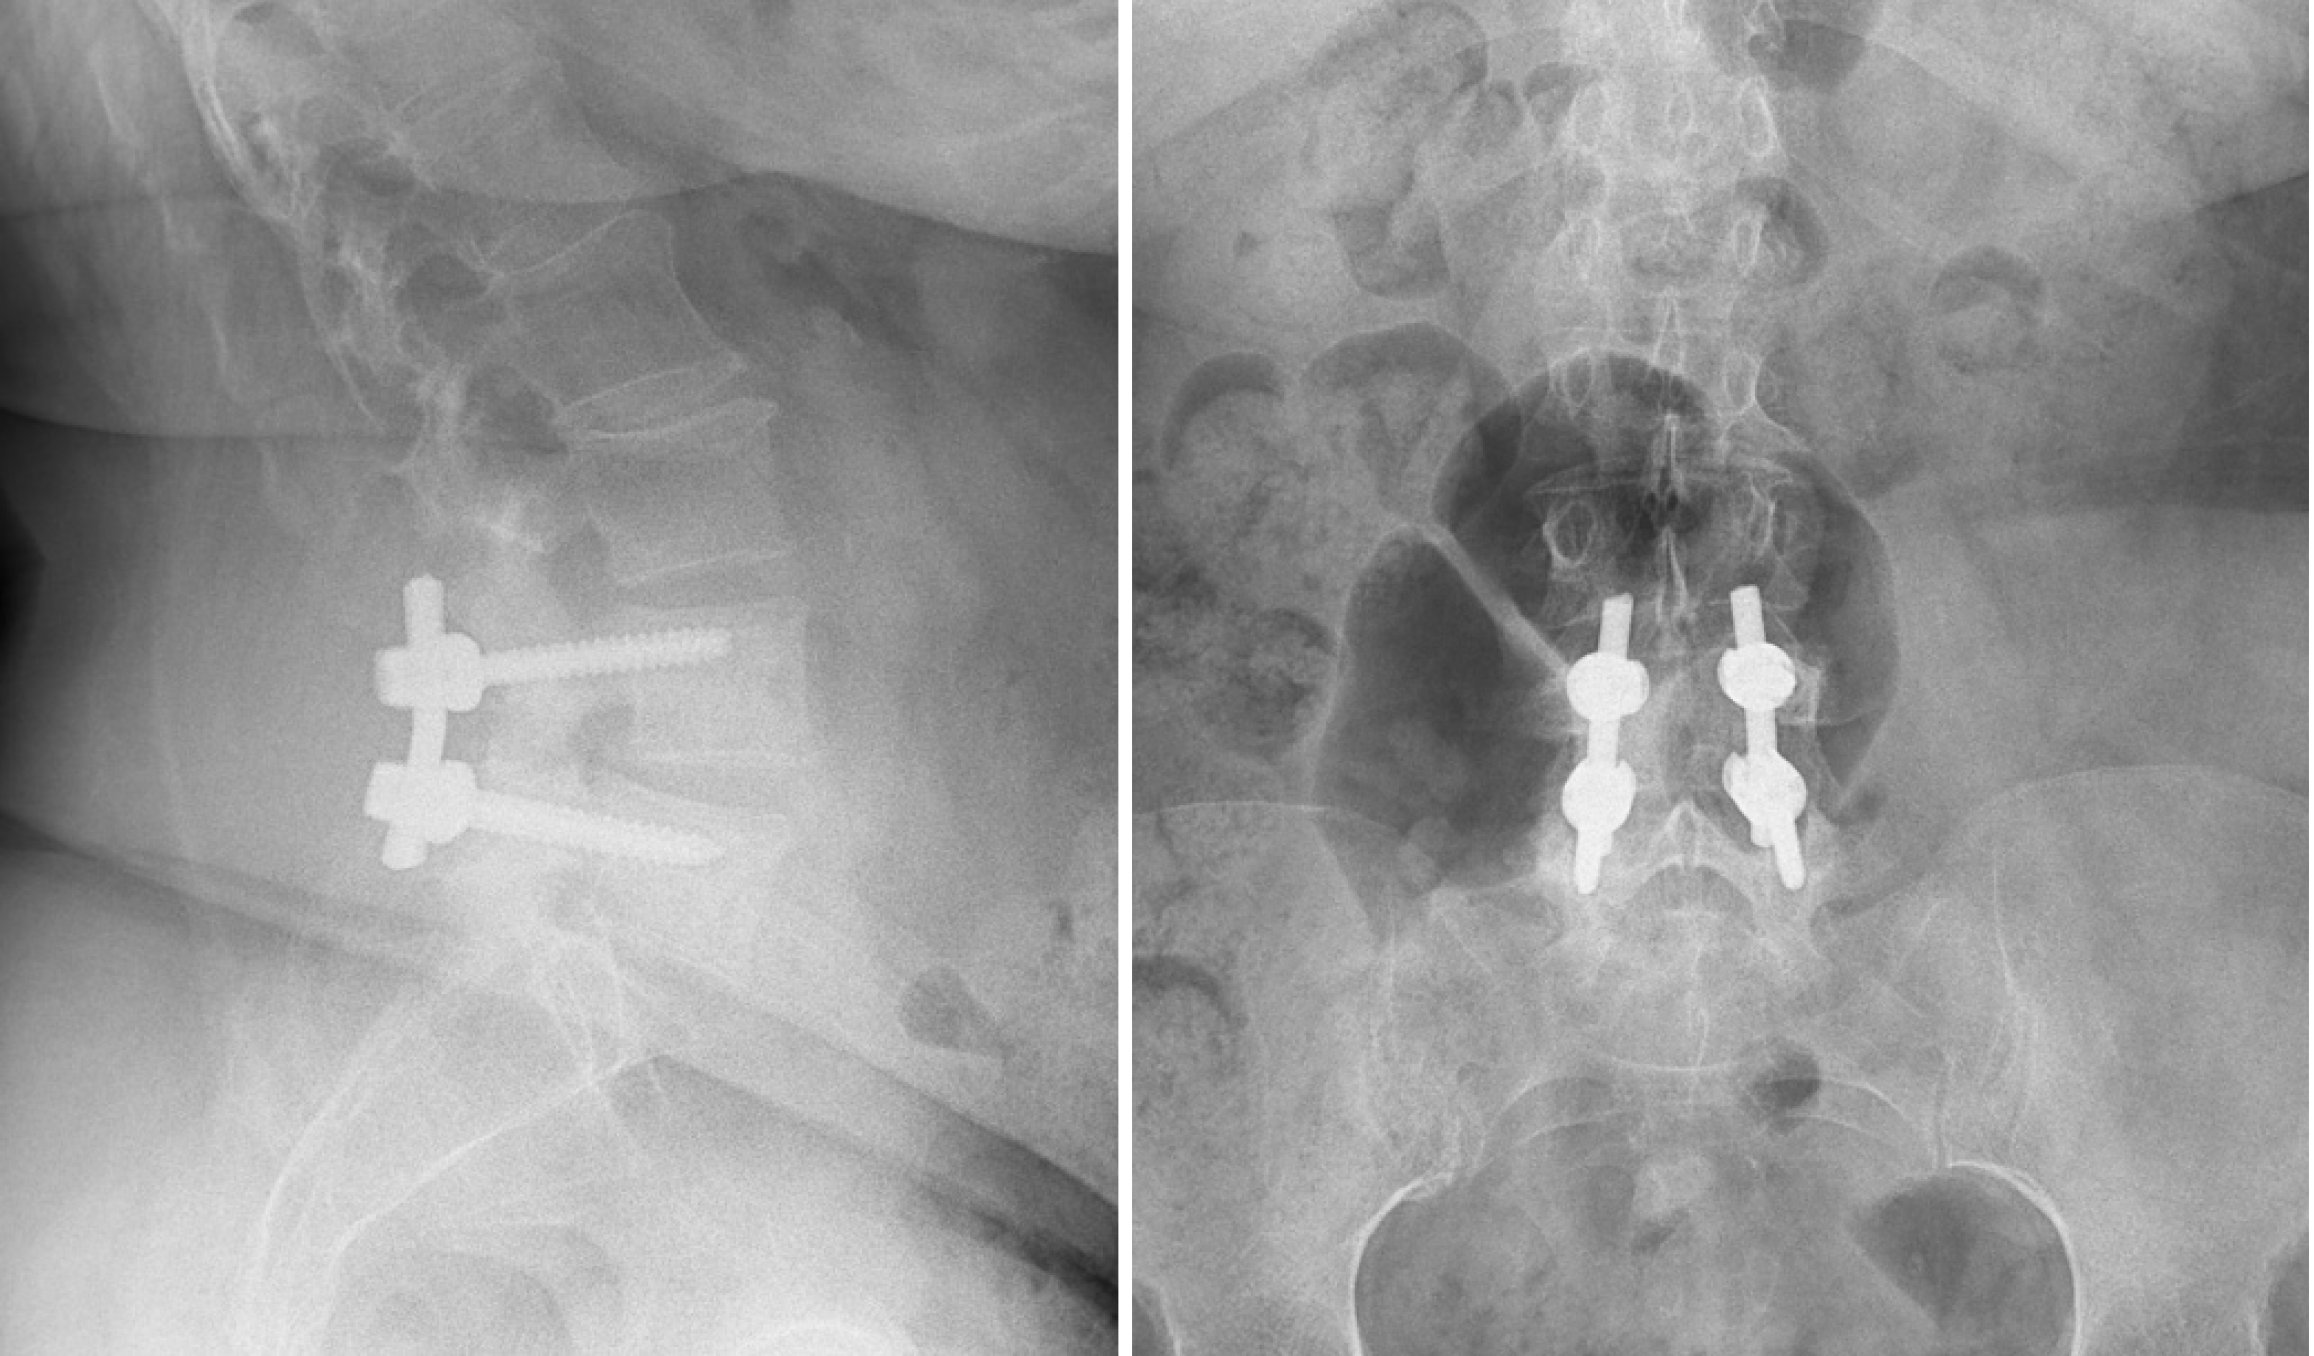

One of the most common causes of lumbar instability is degenerative spondylolisthesis, which usually occurs mostly at the lumbar L4-L5 level due to this segments’ increased mobility and transitional biomechanical forces. It is characterized by forward displacement, called anterolisthesis, of two adjacent vertebras. Saremi et al[18] also reported that the L4-L5 level is most susceptible for degenerative slippage and is detectable on dynamic radiographs. Studies have shown prevalence rates of 5.9% in females and 1.5% in males on dynamic radiographs. Higher rates in elderly patients were found that reached over 25% in women over 60 years old. The female predominance is likely attributed to the greater sagittal orientation of the facet joints and hormonal changes in ligamentous laxity. The pathophysiology involves progressive disc degeneration with height loss, sagittal remodeling of the facet joints, and capsular laxity. These changes reduce the resistance to anterior shear forces and allow for vertebral slippage. Dynamic flexion-extension radiographs remain the gold standard for diagnosing mechanical instability. Lattig et al[19] found that patients with degenerative spondylolisthesis had facet joint effusion on supine MRI (mean size approximately 2.15 mm) that correlated with greater translational slippage, meaning that MRI is a valid indicator of dynamic instability. An example of degenerative spondylolisthesis with associated imaging findings is shown in Figure 1.

Figure 1

Figure 1 Imaging of degenerative spondylolisthesis (Wiltse type III) at L4-L5. A: Sagittal T2-weighted magnetic resonance imaging demonstrating anterolisthesis of L4 over L5 with associated disc degeneration and loss of disc height; B: Axial T2-weighted magnetic resonance imaging at the L4-L5 level showing severe central canal stenosis and degenerative facet changes; C: Lateral radiograph clearly showing the anterior slip.